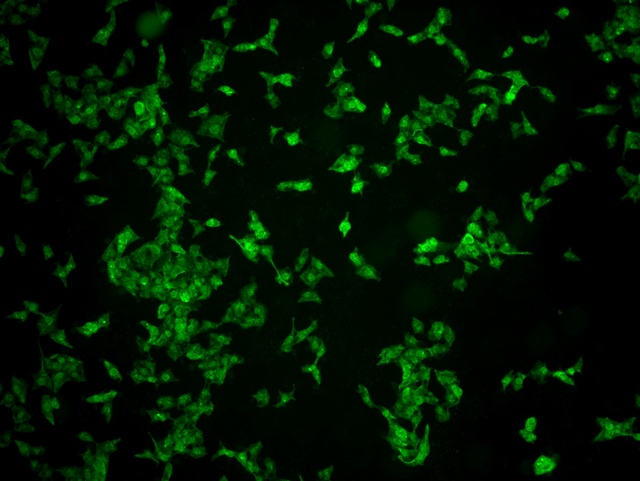

南華大學(xué)在生物醫(yī)學(xué)研究領(lǐng)域一直走在學(xué)術(shù)前沿,近日,該校引進(jìn)Mshot明美的倒置熒光顯微鏡MF52-N,搭配顯微鏡相機(jī)MSX2,為細(xì)胞切片標(biāo)本的研究提供了強(qiáng)大的技術(shù)支持,進(jìn)一步提升了科研實力。

MF52-N倒置熒光顯微鏡以其數(shù)顯LED熒光模塊和深度優(yōu)化的光路設(shè)計,成為細(xì)胞切片觀察的理想選擇。其簡單易用的熒光激發(fā)操作,大大降低了實驗難度,提升了工作效率。同時,該顯微鏡還能提供高質(zhì)量的相襯、熒光和明場成像,確保科研人員能夠捕捉到細(xì)胞切片的每一個細(xì)節(jié)。

在南華大學(xué)的實驗室中,科研人員正借助這套先進(jìn)的顯微系統(tǒng),對細(xì)胞切片標(biāo)本進(jìn)行深入探索。

此外,MSX2顯微鏡相機(jī)的加入,更是如虎添翼。這款相機(jī)以其高分辨率和敏銳的圖像捕捉能力,記錄了實驗過程中的每一個重要瞬間,為數(shù)據(jù)分析與論文發(fā)表提供了有力支持。